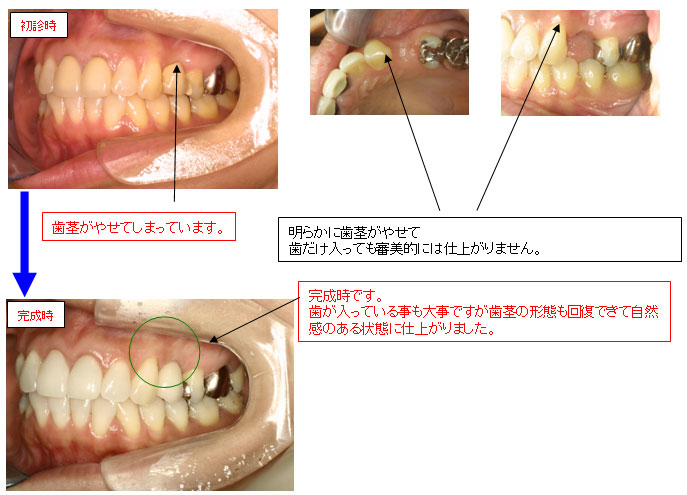

インプラントを用いた審美修復

インプラントを用いた審美修復

歯が欠損して歯茎も陥没している症例です。

インプラントを使って歯を入れるのと同時に歯茎の陥没している状態も改善することが出来ました。

歯が欠損して歯茎も陥没している症例です。

インプラントを使って歯を入れるのと同時に歯茎の陥没している状態も改善することが出来ました。